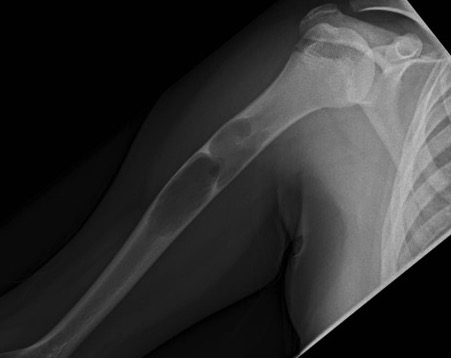

X-ray

Well-defined lucency

- thin sclerotic rim

- usually central

- thinned cortex with slight expansion

- thin internal septa

- can be multi-loculated

Fallen-Leaf (AKA fallen-fragment)

- with pathological fracture

- indicates that the lesion has no matrix and is fluid filled

Fallen leaf sign